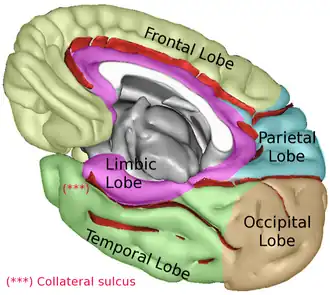

Limbic lobe (shown in purple) of right cerebral hemisphere.

Limbic lobe (shown in purple) of right cerebral hemisphere. -

Limbic lobe (shown in purple) of right cerebral hemisphere.

Limbic lobe (shown in purple) of right cerebral hemisphere. -